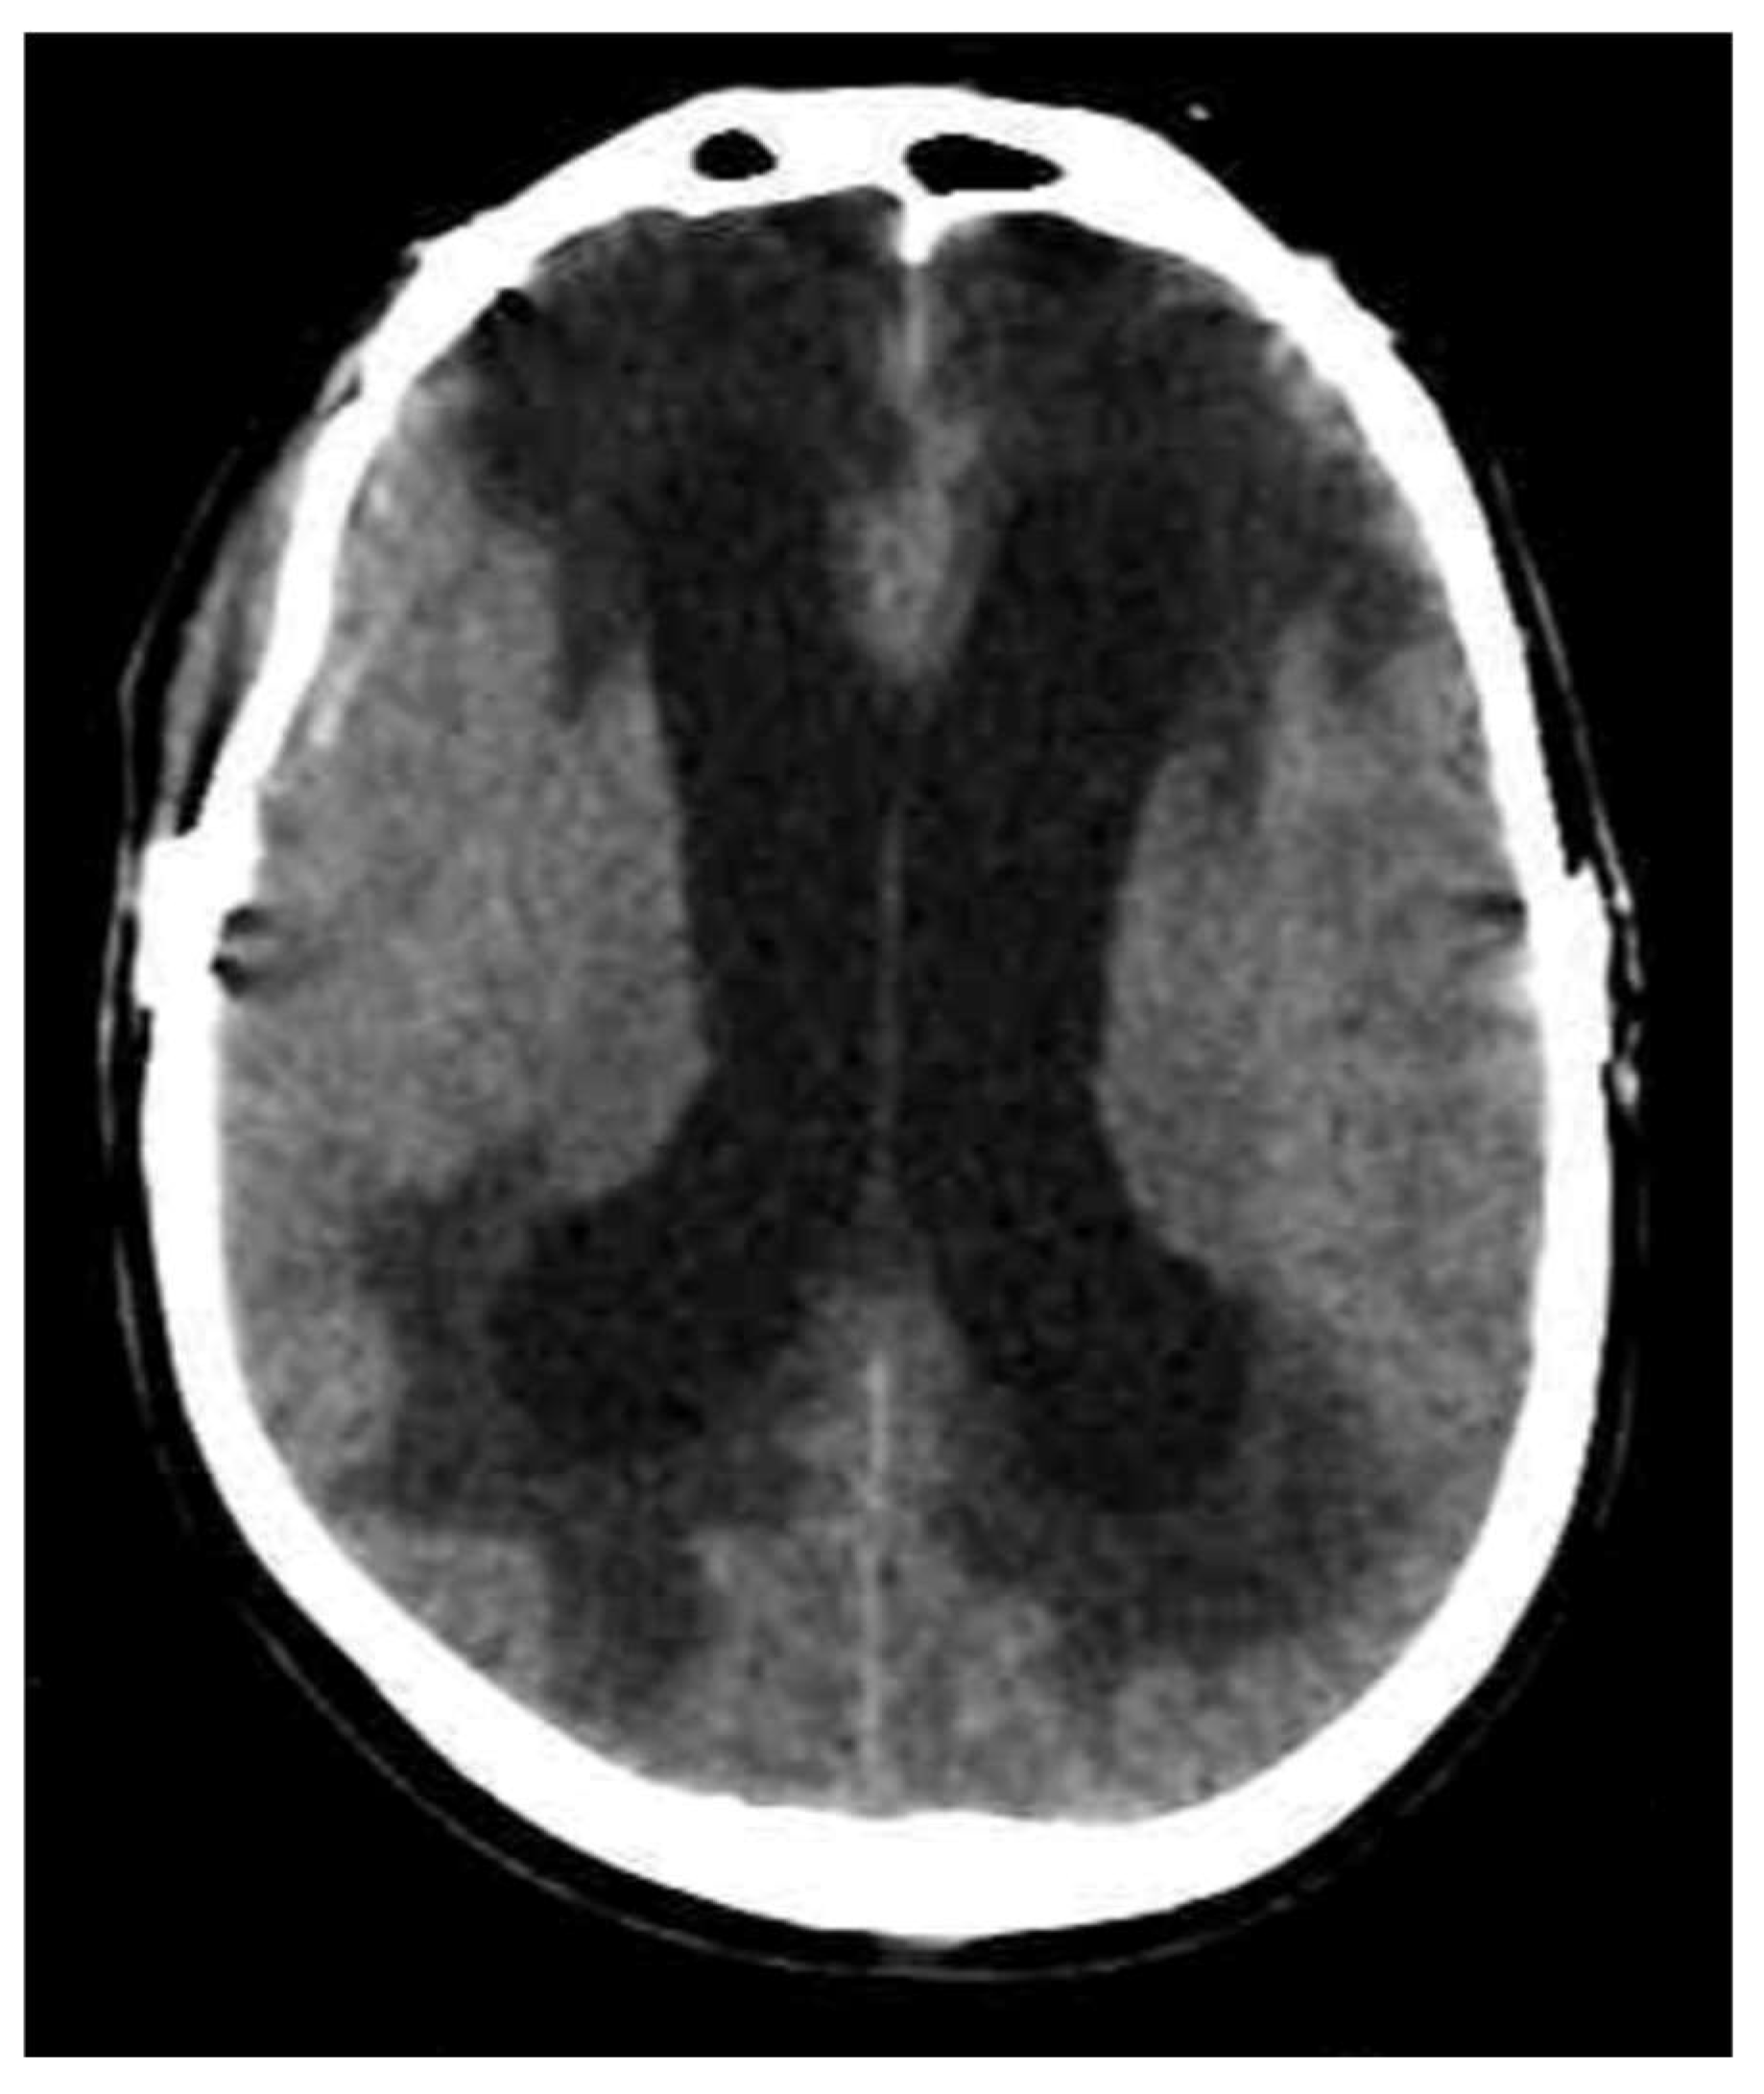

3.4. Interstitial Edema

| Interstitial | Preserved | Interstitial | CSF | Abnormal fluid accumulation in the extracellular space surrounding the cerebral ventricles is caused by an increased pressure within the ventricular system that damages the ependymal lining and generates CSF passage from the intraventricular space to the periventricular extracellular space. | EVD/Ventricular shunt/Endoscopic third ventriculostomy, when identification of the imaging findings. |